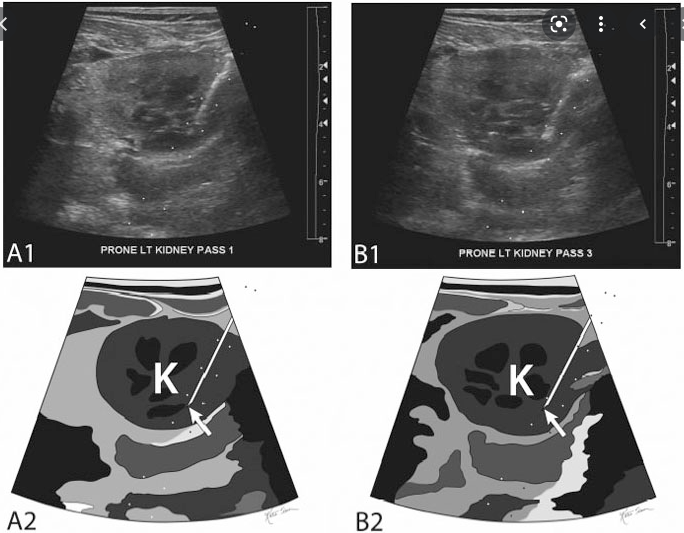

신장은 횡격막 바로 밑에 붙어있기 때문에 숨쉬는 것에 따라 위/아래로 움직이고, 이외 근육과 지방들은 옆으로 움직이게 됩니다. 따라서 아래 그림처럼 숨 쉬는 것에 따라 바늘이 스윙하는 것을 관찰하게 되면 신장에 바늘이 들어갔다고 생각할 수 있습니다.

Blind 방법에서는 환자분께 "숨을 크게 마시고, 참으세요"라고 한 상태에서 초음파로 생각해 놓은 깊이까지 바늘을 진입시키며 스윙을 관찰하는 것이 중요합니다. 스윙이 잘 안보이는 경우 깊이를 조금 조정해볼 수 있으며, 환자에 따라 호흡에 따라 신장이 많이 안 움직이는 사람도 있으므로 스윙이 잘 관찰되지 않으면 초음파를 보는 방법으로 넘어갈 수 있습니다.